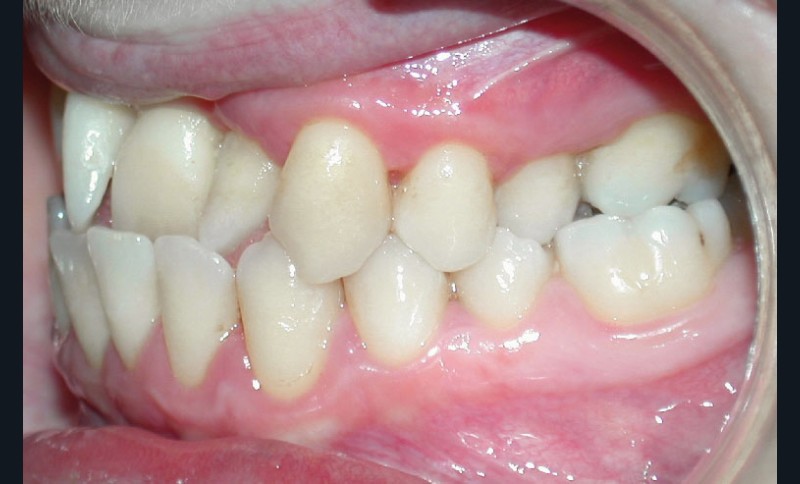

• Malocclusion de classe III d’Angle par rétroalvéolie maxillaire,

• endoalvéolie maxillaire avec occlusion inversée antérieure et bilatérale,

• infraclusion incisive,

• fortes malpositions des incisives supérieures (dont 22 qui est en rotation axiale disto-palatine de 90°), • dysharmonie dento-dentaire (12 en « grain de riz » est aussi en rotation marginale disto-palatine de 45°),

• anomalie de la forme d’arcade maxillaire, 47, 18 et 28 sont absentes. (fig. 1 à 8), 48 est positionnée très postérieurement, quasiment au niveau de la branche montante (fig. 9 et 11).